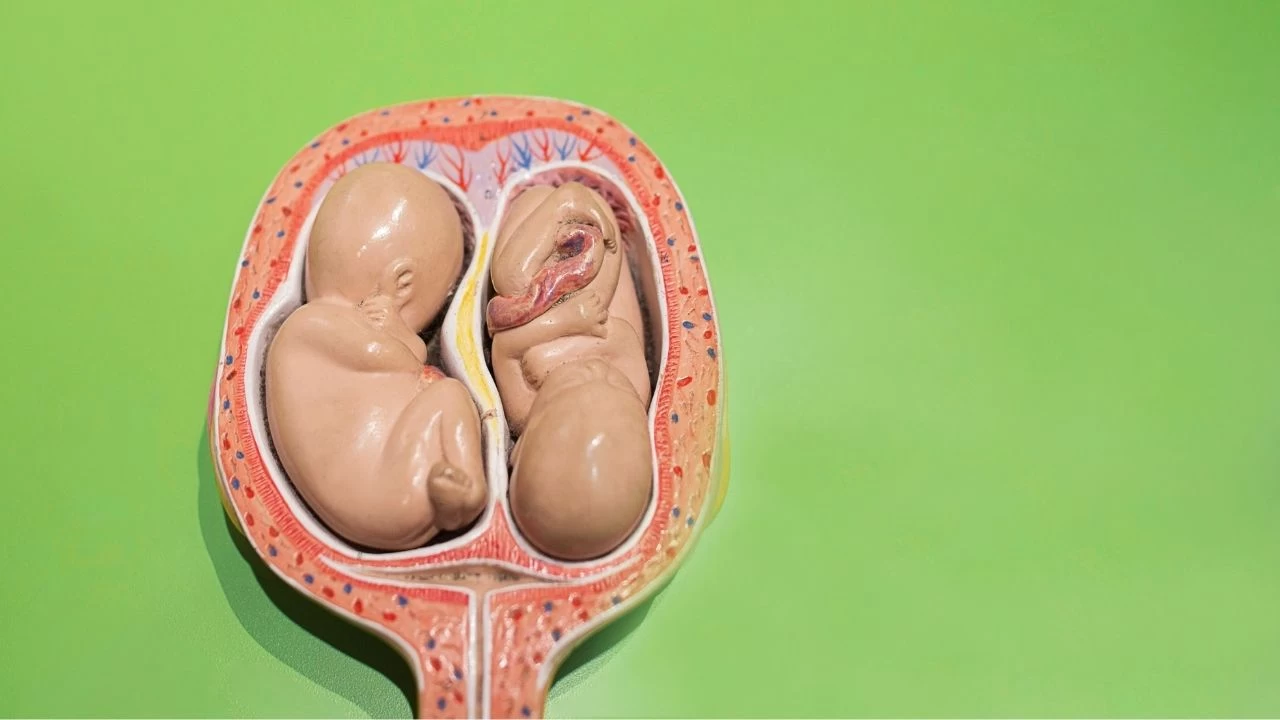

Cenin ve Embriyo Arasındaki Fark

| Özellik | Embriyo | Cenin |

|---|---|---|

| Dönem | İlk 8 hafta | 8. haftadan doğuma kadar |

| Gelişim Özellikleri | Organ temelleri atılır | Organlar büyümeye devam eder |

| Görünüm | Hücre kümelerinden oluşur | İnsan formu belirginleşir |